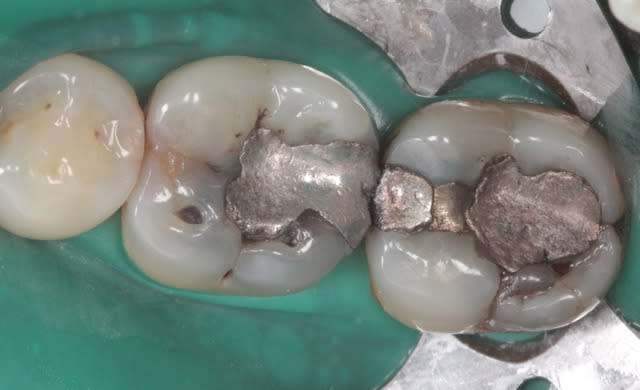

ca parait encore carié sur les photos :-(

tu controles avec quoi pour faire la différence entre coloré et carié ?

je vérifie à la sonde, et je travaille sous loupe 3.6.

Mais je suis d'accord avec toi cela fait souvent cet effet en photo. On arrive à un grossissement plus important qu'avec les loupes, et on voit mieux sur la photo. Pas impossible que j'ai laissé des zones atteintes.

Elles seront fermées hermétiquement sous la résine. C'est que je me dis pour m'endormir ;)